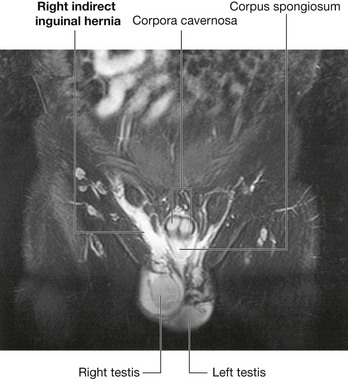

The hernial sac of an indirect inguinal hernia enters the deep inguinal ring and passes through the inguinal canal. If the hernia is large enough, the hernial sac may emerge through the superficial inguinal ring. In men, such a hernia may extend into the scrotum (Fig. 4.51).

Fig. 4.51 Right indirect inguinal hernia. T2, fat saturated, weighted magnetic resonance image in the coronal plane of a male groin.